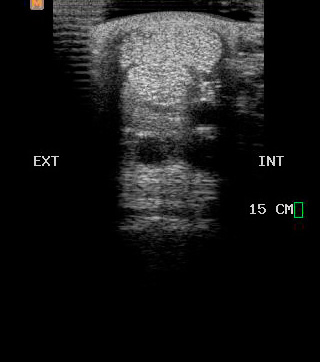

Ecografía

Cuenta con Ecografía digital de alta complejidad.

17 años de experiencia siendo una de las ecografistas más reconocidas en la práctica de equinos. Realiza pasantías en la universidad de Davis California y en Mid-Atlantic Equine Medical Center en New Jersey.